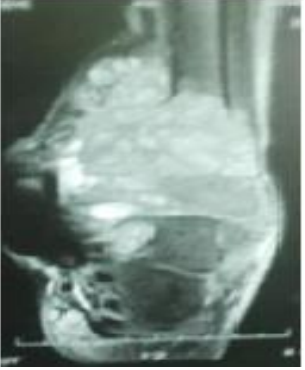

We report the case of a 37-year-old young man with no notable pathological antecedents who presented at the orthopedic consultation for a painful swelling of the left distal tibia and fibula that had been evolving for 5 months and without any alteration of the general state. There was change in color and consistency of the skin with respect to the tumor action. On physical examination, there was a dorsoflextion blockage of foot because of the large volume occupied by the tumor mass and the articular destruction at the level of the distal tibio-fibular joint; plantar flexion estimated at 10˚ and dorsal flextion at 3˚; inversion at 5˚ and eversion at 2˚. The x-ray showed a lesion with blurred boundaries, extending into the soft tissue that is not limited by a bony shell; with destruction of the cortex, invasion of soft parts and honeycomb pseudo-partitions (Figure 1-2). And finally the Magntic Resonant Imaging (MRI) of the left leg showed (Figure 3-4-5-6) a lysis of the cortex of the lower extremity of the leg. It corresponds to grade 3 of the Campanacci and Merled ’Aubignee classification. A complete surgical resection below knee amputation (BKA) was offered to the patient. Under spinal anesthesia, this incision was made proximally to expose a healthy portion of the leg bone. Surgical removal of the tumor by BKA a proximal resection of the tibia and fibular bone by about 2 cm in the healthy zone. The anatomopathological assessment (Figure 7) showed abundant mononuclear cells and discrete nuclear anomalies with marked mitotic activity, but without atypical forms. The histological examination of the bone fragments confirmed a grade 3 giant cell tumor according to Sanerkin, Jaffe Lichtenstein and Pottis. CT scan was done to exclude pulmonary metastases (Figure 8). At three weeks removal of suture and start physiotherapy of knee. Surgical treatment with the excision of the large tumor mass by BKA improved the function of the leg and general condition of the patient.

Figure 3: MRI report demonstrates heterogeneous lesion involve distal tibia and fibula.

Figure 4: MRI Show heterogeneous lesion involve distal tibia and fibula.

Figure 5: MRI Show heterogeneous lesion involve distal tibia and fibula with cortical break posteriomedially.

Figure 6: MRI Show heterogeneous lesion involve distal tibia and fibula with fatty infiltration and enhancement of blood vessel at medial site.